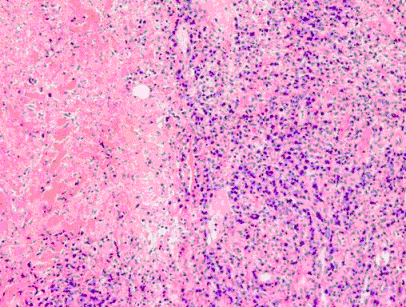

患者男,67岁,因“体检超声发现右肝占位2个月”来诊。患者既往有慢性肝病22年。实验室检查:血AFP轻微增高。CT:右肝有一直径2cm肿块,如图所示。

可能的病理诊断为()。(提示行CT引导性穿刺活检,组织学形态如下图所示。)